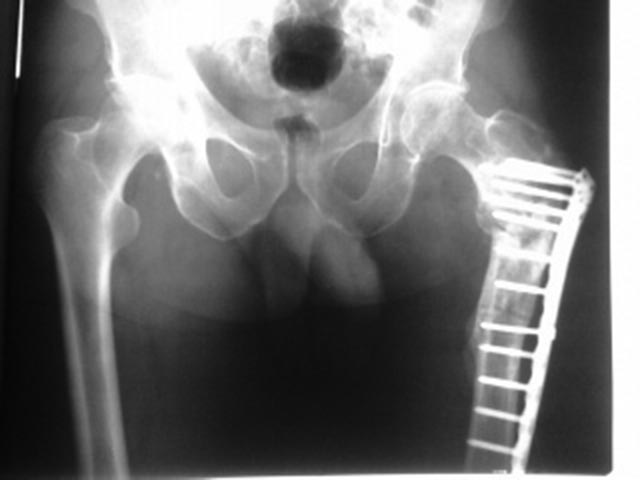

[Ortho] Ложный сустав вертельной области, варусная деформация

Дополнительные рентгенограммы